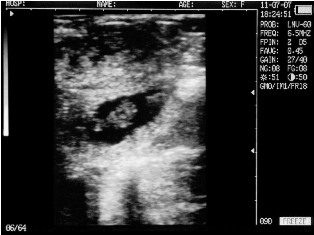

Endometritis in the uterus of the cow